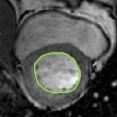

4.2 Visual assessment

We select the case that achieves the highest and lowest dice score for visual assessment. Fig. 4 shows example segmentation results where the proposed method achieved the highest agreement with the ground truth delineations. Fig. 5 shows example segmentation results where the proposed method achieved the lowest agreement with the ground truth delineations.